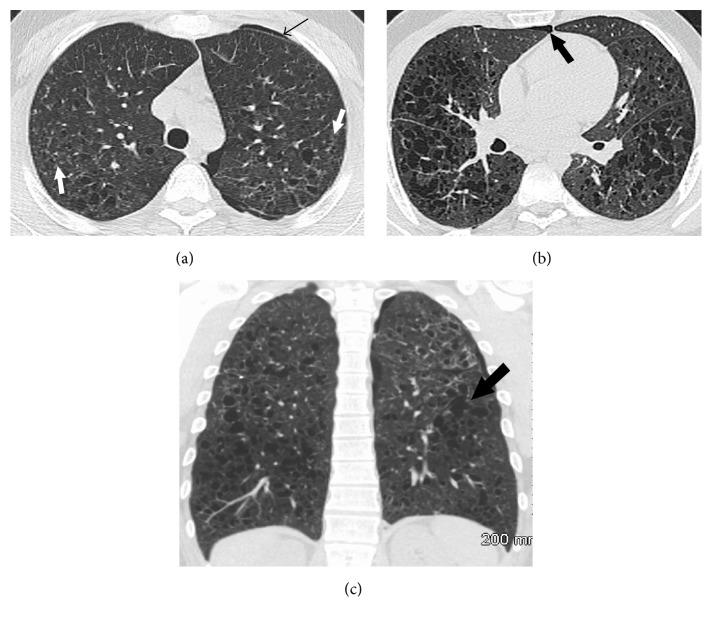

Langerhans cell histiocytosis is characterized by the abnormal nodular proliferation of histiocytes in various organ systems. Pulmonary involvement seen in young adults is nearly always seen in the context of past or current cigarette smoking. Although it tends to be a single-system disease, extrapulmonary manifestations involving the skin, bone, and hypothalamic-pituitary-axis are possible. High resolution CT (HRCT) of the thorax findings includes centrilobular nodules and cysts that are bizarre in shape, variable in size, and thin-walled. Often the diagnosis can be made based on the appropriate clinical presentation and typical imaging findings. Treatment includes smoking cessation and the potential use of glucocorticoids or cytotoxic agents depending on the severity of disease and multisystem involvement.

朗格汉斯细胞组织细胞增多症的特征是组织细胞在各个器官系统中出现异常的结节状增殖。在年轻成年人中出现的肺部受累几乎总是在过去或当前吸烟的背景下出现。尽管它往往是一种单系统疾病,但累及皮肤、骨骼和下丘脑 - 垂体轴的肺外表现也是可能的。胸部高分辨率CT(HRCT)表现包括小叶中心结节和囊肿,其形状怪异、大小不一且壁薄。通常根据适当的临床表现和典型的影像学表现即可做出诊断。治疗包括戒烟,以及根据疾病严重程度和多系统受累情况可能使用糖皮质激素或细胞毒性药物。